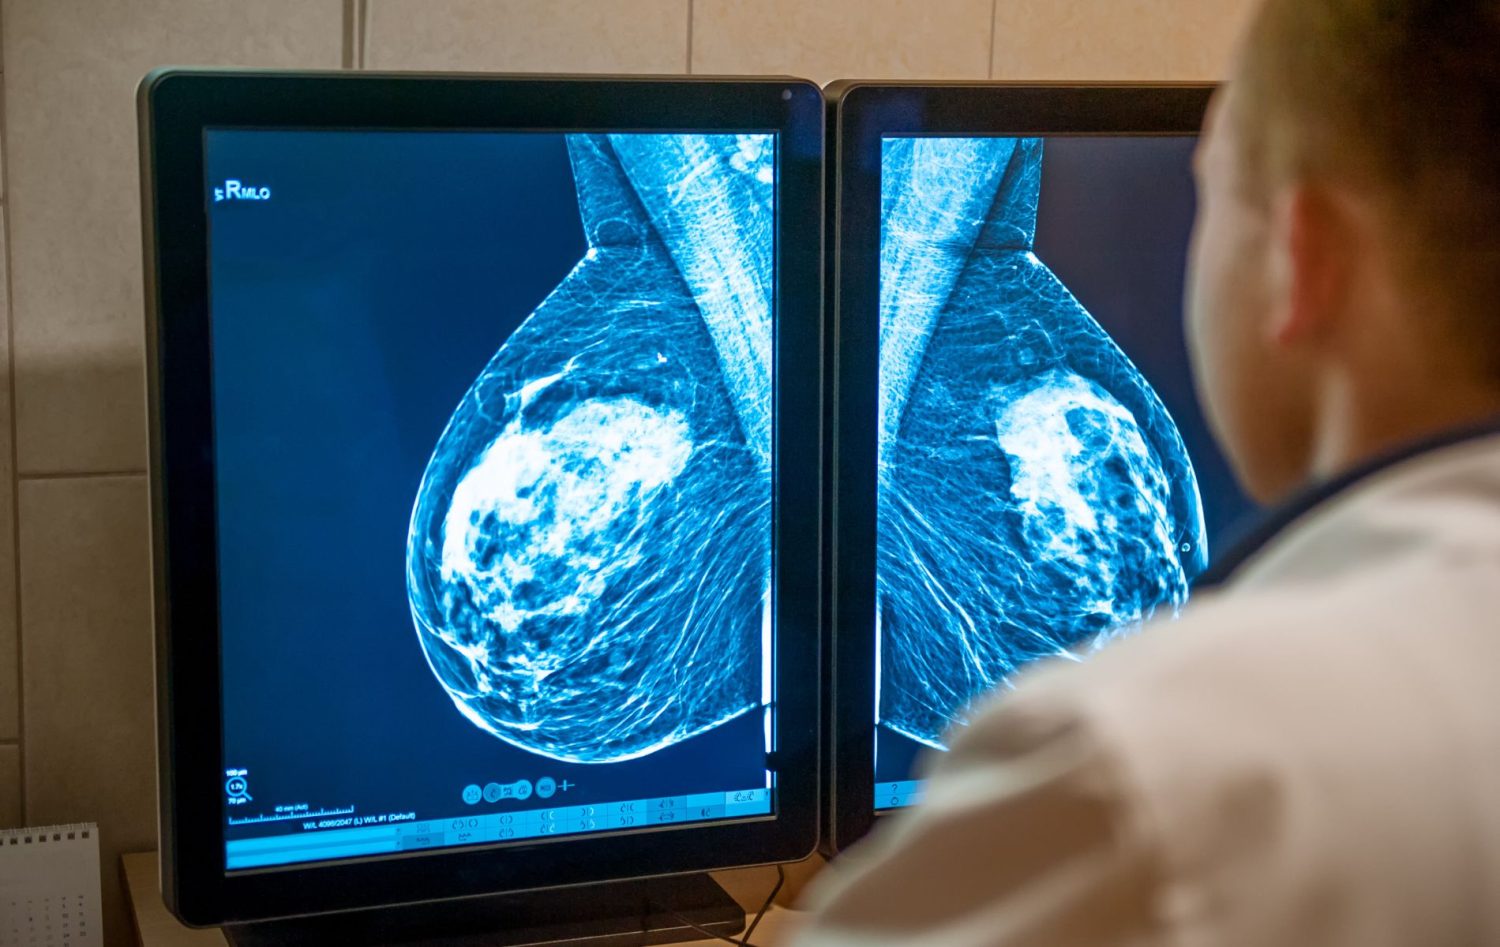

Un avance científico revolucionario podría cambiar el rumbo en la lucha contra el cáncer, especialmente en el caso del cáncer de mama. Investigadores han logrado identificar mecanismos clave que explican cómo las células tumorales de cáncer de mama tienen la capacidad de migrar a otros órganos y permanecer latentes, dando lugar a la temida metástasis. En España, se espera que en 2023 se diagnostiquen 35.001 nuevos casos de cáncer de mama, con alrededor de 6.600 muertes, muchas de ellas debido a la recaída con metástasis. Este descubrimiento científico ofrece nuevas esperanzas y perspectivas para combatir la metástasis y mejorar la vida de quienes padecen esta enfermedad devastadora.